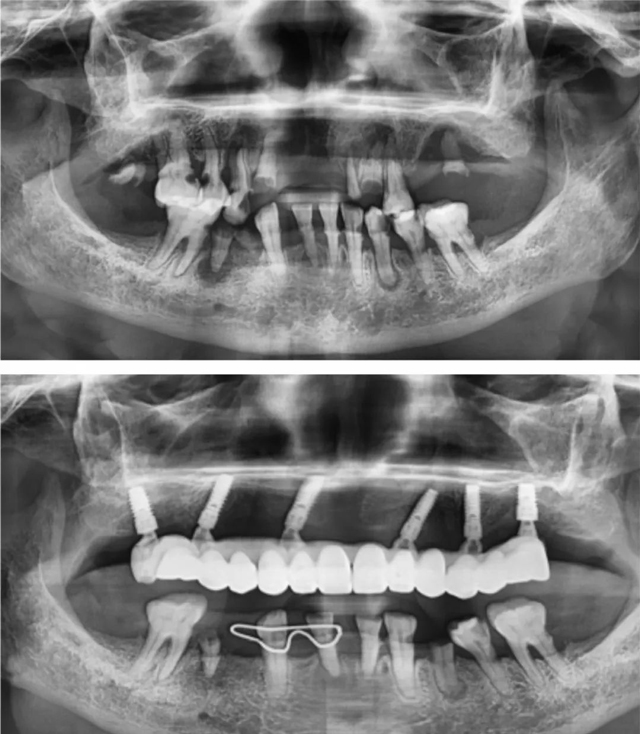

患者術前術后全景片